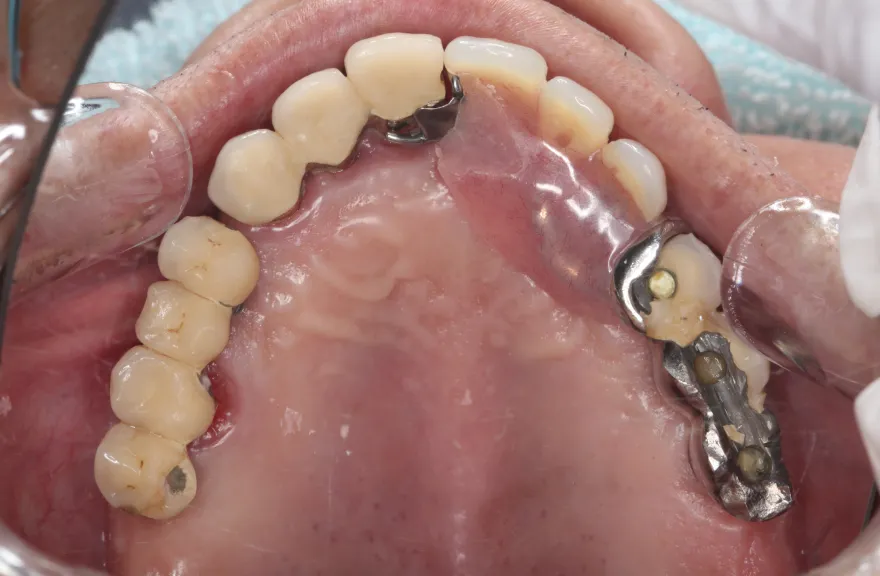

【治療例 3】奥歯が痛い、全体的にみて欲しい 60歳

今まで何回歯を入れてもトラブルが起きるために、奥の歯を入れないまま今日に至る、ということでした。

噛み合わせ・骨格を読み解き、今後の人生でトラブルが起きにくいように全体的な治療計画を練りました。 - 治療費用・方針

骨格の前後的な差がある方でした。術前のレントゲンより、上下で歯牙の損傷に明らかな差があるのがみてとれます。

上の歯がないところにインプラント治療を行い、上顎は全てインプラントフィクスチャーによる固定性の歯を入れられることも費用的には可能な方でした。

今回の症例では、敢えて上顎は総義歯形態をとり、骨格的な前後の差を解消するよう工夫しました。

上顎の残っていた歯も、差し歯としては使えずとも、敢えて根だけ残すことによって組織を温存し、義歯の安定に寄与するよう設計しました。